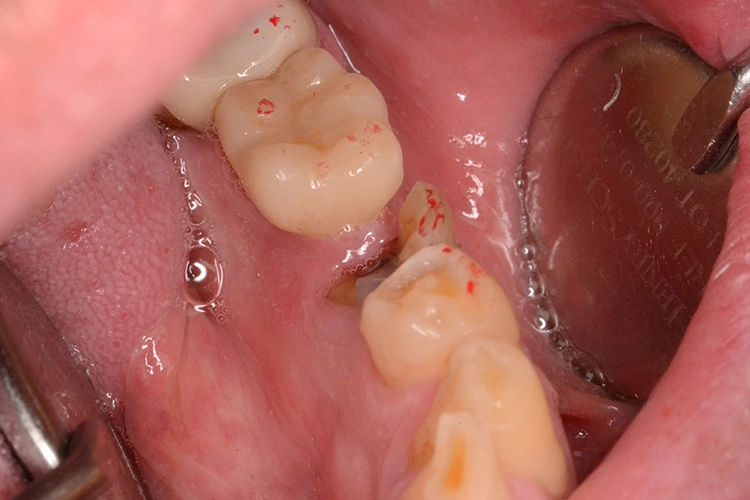

Bei diesem 49-jährigen, allgemeinanamnestisch unauffälligen Patienten liegen diverse ästhetisch störende Zahnstellungsanomalien vor, wobei Zahn 21 bei extremer Elongation frakturierte (Abb. 2a). Nach einer Übergangsversorgung mittels provisorischer Stiftkrone (Abb. 2b) entschied sich der Patient für eine Zahnentfernung bei gleichzeitiger Implantation. Im Ausgangs-DVT (Abb. 2c und d) zeigt sich im Cross-Sectional, wie weit der Processus alveolaris zurückliegt.